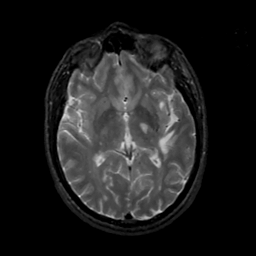

MR Study #12, May 12, 1991 -- Slice #25